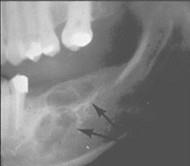

问题 女性,50岁,反复发作尿路结石,骨痛,骨骼X线示骨膜下皮质吸收。实验室检查:高钙血症,血清碱性磷酸酶↑,皮质醇抑制试验血清钙不下降。诊断考虑()

选项 A.原发性甲状旁腺功能亢进症 B.继发性甲状旁腺功能亢进症 C.三发性甲状旁腺功能亢进症 D.骨软化症 E.维生素D缺乏症

答案 A